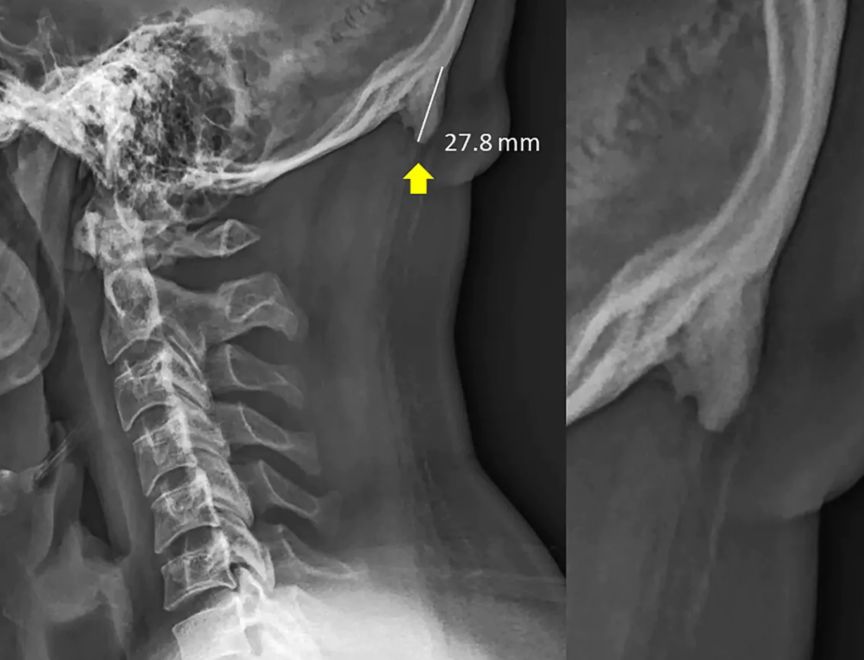

“关注啦!关注啦!看手机看多了,脑袋后面可能会长角!”

这个研究来自澳大利亚阳光海岸大学的一个医生,David Shahar。他在过去20年从医的经历中,发现越来越多的人,在后脑勺窝里、颈子上面的地方,出现了一个小小的凸起。这玩意儿,学名为“枕外隆凸”(external occipital protuberance)。他发现了这个现象之后,和同事一起“看了各个年龄的1200多张X光片”,发现在18-30岁的人中,这块小骨头出现的频率“异常高”。最大的一个枕外隆突案例,“角”甚至凸出来了接近3厘米。

然后,判定长出枕骨隆突(原 paper 根本没说“长角”,毕竟动物的角和骨骼的成分根本不同)的标准在10毫米,只要超过这个值,就在数据中算作是阳性,而不一定真的长“出来”了那个东西,文中配图里的案例其实非常极端。研究者把这些X光片按年龄和性别分了组,发现年轻人当中长出枕骨隆突的人要多一点点:35%的30岁以下的年轻男性有这个隆突,而在30-50岁的视察者中,此比例不到15%。